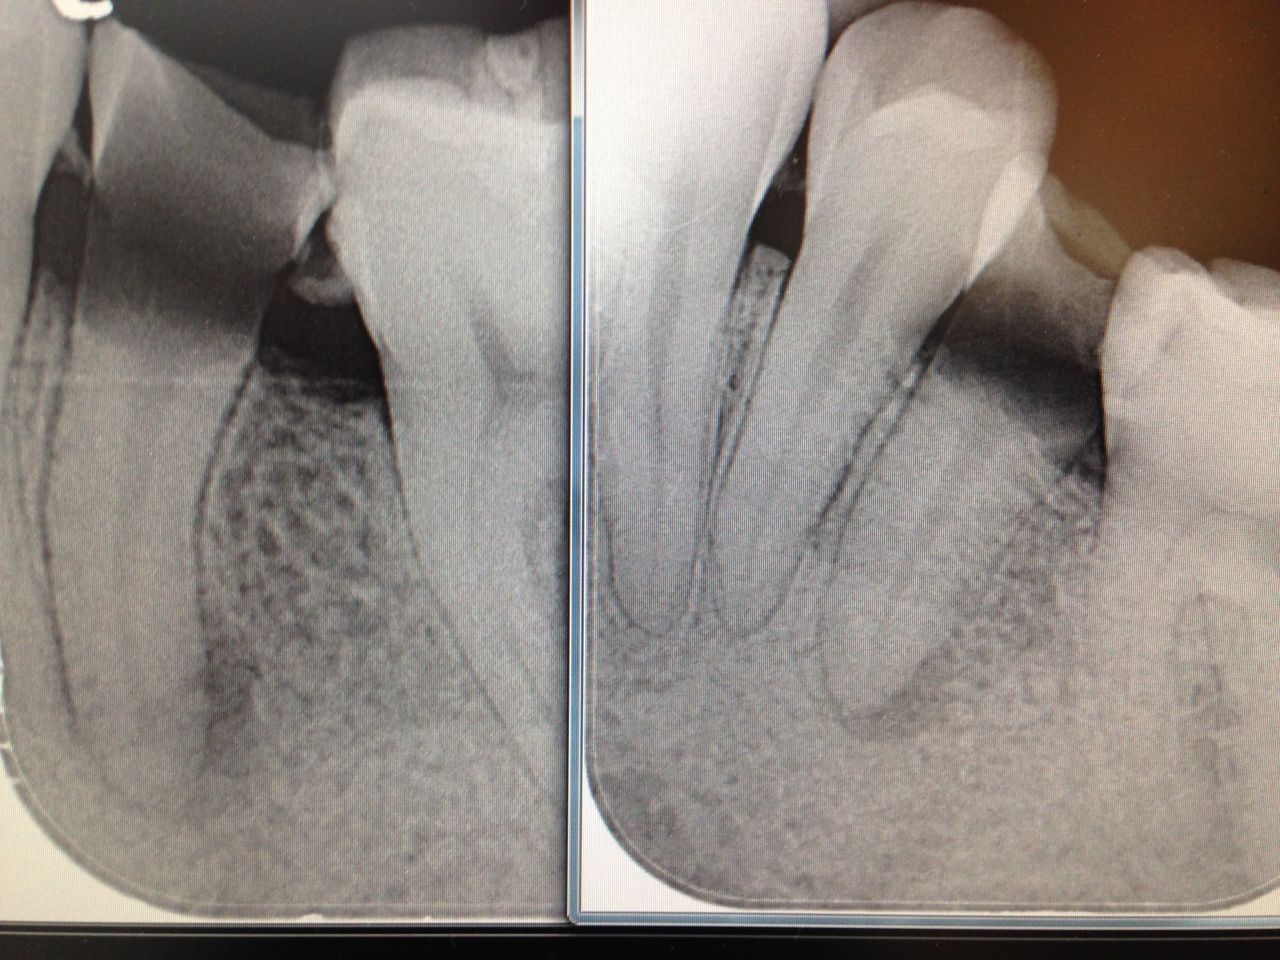

神経の管にはレントゲンや手術用顕微鏡でも見えない細いクダがたくさんあります。

歯科医が消毒できるのは、せいぜいレントゲンで見える本管、木の幹のような部分だけです。

細く分かれた枝や葉にまで入り込んだ最近は取り除けません。

消毒薬をしみ込ませるのが、せいぜいできる事なんです。